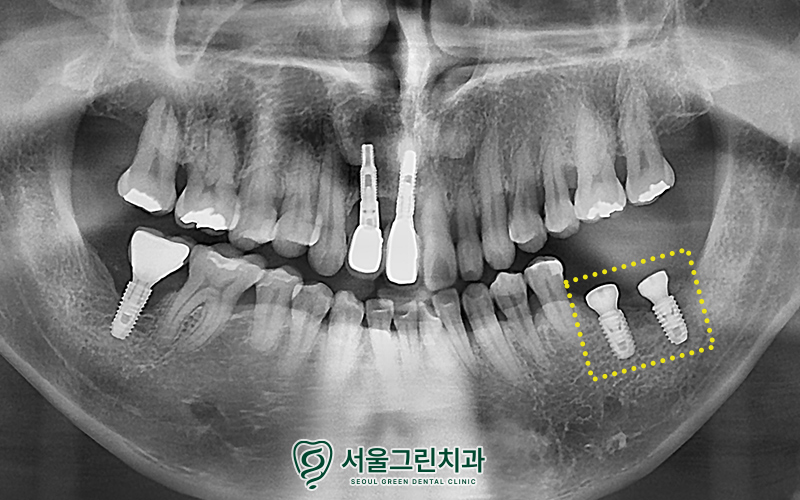

기존 임플란트 발거 후

주변 염증 조직까지 말끔하게 제거 하고,

뼈이식을 병행하여

임플란트 식립을 진행한 모습입니다.

뼈이식을 통하여

안정적인 기반을 만들어준 후,

현재 인공치근인 픽스처를 식립해준 상태인데요.

임플란트가 잇몸뼈에 잘 고정될 수 있도록

충분한 유착기간을 거친 후

크라운(보철물) 셋팅을 도와드리기로 했습니다.